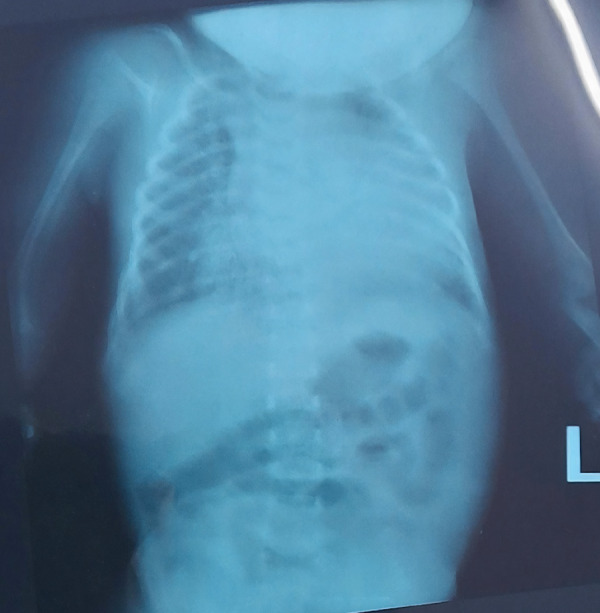

Case summary: We report a 2-week-old term neonate with bilateral phocomelia, micrognathia, jaundice, and low birth weight. The pregnancy was unremarkable, with no thalidomide exposure. The mother had a history of early pregnancy losses. Clinical evaluation revealed absent humeri and radii bilaterally, with hands attached proximally to the trunk. Genetic testing was not performed, limiting the identification of underlying etiology. The patient was managed with supportive care, parental counseling, and planning for long-term rehabilitation. This case underscores the importance of multidisciplinary care in managing congenital anomalies. Genetic evaluation is crucial in unexplained congenital anomalies. Routine detailed ultrasounds in high-risk pregnancies aid in early diagnosis and parental preparedness.